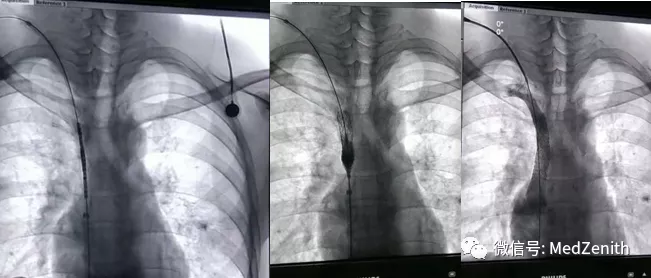

第一次手术于2020年07月15日进行,术中行上腔静脉球囊扩张术,暂时为上腔静脉打开通道,扩张后再次造影测量狭窄段长度为60mm。

第二次手术于2020年7月22日进行,术中选用了2根Pul-stent M40的支架叠加成60mm长支架压握在球囊上,成功进行了支架植入术。上腔静脉压力由术前的20毫米汞柱下降为8毫米汞柱,与右房压相同。术后造影显示,术前由于上腔静脉闭塞而引起的大量静脉侧枝随之消失,上腔静脉血流回流通畅,病人也再未出现头面部肿胀以及肠梗阻现象。术后给予口服阿司匹林+氯吡格雷双抗治疗3个月。